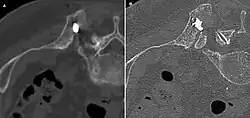

Scanner d'une métastase ostéocondensante dans l'os du crâne d'un patient souffrant d'un carcinome de la prostate. On reconnaît clairement l'extension de la métastase au-delà des limites initiales de l’os.

Par comparaison, scanner de métastases ostéolytiques dans l'os du crâne d'une patiente souffrant d'un cancer du sein. On distingue une ostéolyse plus grande sur le front, et plusieurs plus petites.